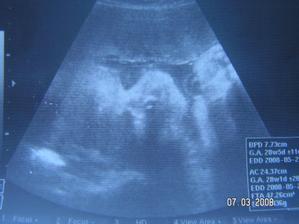

Tak jsme zpět z poradny.Jestli to bude kluk nebo holčička nevíme,protože miminko překřížilo nožky a nechtělo se ukázat.Za to na mamku krásně mávalo,tak to pan doktor zvěčnil-fotka je v albíčku.Měříme už 11cm!!!Zítra - 14.11. jdeme na tripple testy a taky na kontrolu,mamce totiž začalo nějak tvrdnout bříško,tak to pan doktor raději zkontroluje.Snad je všechno v pořádku.///Tak dneska 14.10.-na kontrole všechno v pořádku,jen placenta je trochu moc dole,ale to by se mělo do dvou měsíců upravit,mimi je o pět dní menší,ale krásné.(viz. foto).Dostali jsme magnézko na to tvrdnutí.Nabrali mi krev na tripple testy,tak se bojím,aby to bylo v pořádku.///Tak na testech jsme měli nakonec něco mírně zvýšené,ale celkem ještě v normě,tak doufám,že 12.12. na velkém genetickém UZ bude všechno v pořádku.A třeba se už konečně dozvíme,co to vlastně čekáme.///Tak jsme byli na genet.UZ-všechno je naprosto v pořádku!!!Mimi váží 360g a měří 25cm.Jsme 20+5tt.A víme,co to bude!Holčička!!!///Narazila jsem na úžasný kočárek,byla jsem z něho tak unešená,že jsme ho malé Fazolce museli pořídit.///7.1.-KO v poradně.Princezna má už 633g!!Všechno je v pořádku.Příští týden na cukrovkový test-FUJ!Můj váhový přírustek zatím 4,5kg-24+6tt.///Včera-4.2. kontrola v poradně.Všechno v pořádku.Vážíme 1255g a měříme přes 30cm.Můj váhový přírůstek - 29.tt.-asi 5,5 kg.///3.3.2008-velký UTZ,všechno v pořádku,akorát mám špatný krevní obraz,takže budeme zobat železo.Můj váhový přírůstek 7kg-33.tt.////